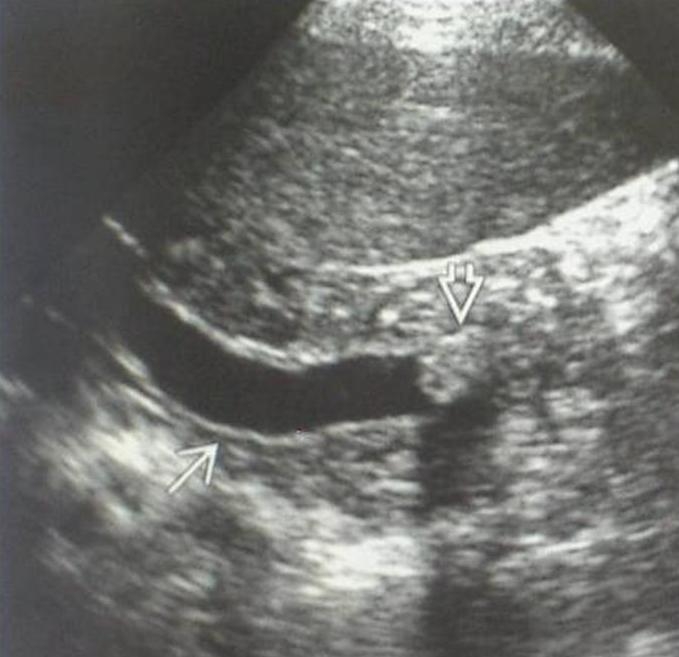

The echogenicity of the normal liver tissue is mildly hyperechoic (Figure 3) due to the intrahepatic connecting tissue structures, small veins, arteries and bile ducts (its echogenicity is principally comparable with the adjacent normal right kidney cortex, the liver has a bit hyperechoic structure than the right kidney, and its echogenecity is principally the same as the spleen's).

Figure 3: Normal liver, 2D US image

The portal vein and its branches have hyperechoic walls which can be easily differenciated in the liver structure. The walls of the hepatic vein branches have remarkable less echogenecity. The normal diameter intrahepatic bile ducts and the smaller liver arteries cannot be imaged and observed. The wall of the hepatic ducts and the main biliary duct (ductus choledochus) is also moderately hyperechoic. The hepatic hilum consists of the „double barrel” configuration (main biliary duct – portal vein, inbetween the cross-sectional view of the hepatic artery trunk) in the typical anatomical location, using an appropriate longitudinal plane.